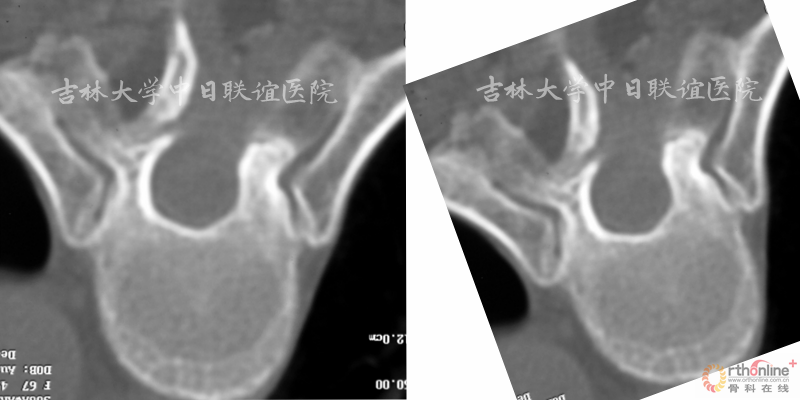

2.暴露目标节段半椎板,开一个宽约1-1.5cm的窗口(如下图) 。

3.沿患者长轴方向将手术台向术者对侧倾斜15-20度(如下图) 。

3.2 半椎板显微操作下肿瘤摘除术:肿瘤摘除的同时尽可能保留脊柱的稳定性;

优点:创伤小、出血少

卧床时间较短、恢复较快

减少长期卧床引起的并发症

减少远期脊柱不稳与后凸畸形的优点

缺点:手术视野有限,术者需要借助显微镜及纤维操作器械进行手术,对术者显微操作技术要求较高。

手术技巧:

1.可先行肿瘤包膜内切除减压,然后于周围正常结构与肿瘤的间隙处切除肿瘤;

2.术中用双极电凝确切止血;

3.肿瘤包膜完整且界限清楚(如神经鞘瘤)可实施完整切除;